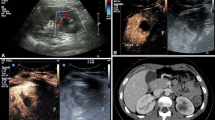

Contrast-enhanced CT images in the portal venous phase, in the axial view, showing a 46-year-old female with lymphoma and sepsis due to infection (qSOFA 2). A thickened and hyperdense bowel wall can be observed (a, arrows), with peripancreatic oedema (b, arrows), reduced and inhomogeneous liver enhancement (c), and enlarged kidneys with abnormal enhancement (d, arrows)

Bowel hypoperfusion (shock bowel)

The most frequent findings associated with shock bowel include fluid-filled, dilated loops with thickened walls (> 3 mm) due to oedema of the submucosa and increased mucosal enhancement relative to the psoas muscle (Figs. 2b, 4a). Changes to the small intestine are the most commonly observed characteristics among the CT signs indicative of shock. The small intestine is often diffusely involved in the occurrence of hypotensive shock, whereas the colon is rarely involved [23,24,25,26]. The shock bowel symptoms occur due to systemic hypotension, with consequent sympathetic stimulation, resulting in splanchnic vasoconstriction and a reduction in intestinal perfusion. These effects reduce the supply of oxygen to the tissues, altering permeability and causing the hyperenhancement of the mucosa and the oedematous thickening of the intestinal wall and submucosa. The reduced reabsorption of fluids causes the luminal distension of the intestinal loops. The recognition of the shock intestine is essential to avoid confusion with other conditions, such as intestinal ischaemia due to vascular occlusion, which are associated with different CT characteristics. The most challenging differential diagnosis is diffuse bowel ischaemia due to vascular occlusion, which can also present with bowel-wall thickening and luminal distension. Unlike the shock bowel, bowel ischaemia due to arterial occlusion is not associated with the hyperenhancement of the mucosa or the congestion of the wall. Mesenteric venous occlusion may show both of these CT signs, however, in combination with a filling defect of the superior mesenteric vein or its branches, mesenteric congestion, and stranding [23]. In addition, CT signs associated with hypotension complex can be important indicators of systemic hypotension, which may facilitate the differential diagnosis. Shock bowel has a mortality rate of up to 70% [23,24,25,26, 28,29,30,31].

Peripancreatic oedema and abnormal pancreatic enhancement (shock pancreas)

Shock pancreas appears as an abnormal, post-contrast attenuation, with higher than normal density values (20 HU greater than the liver and spleen) and the presence of peripancreatic low-density fluid (< 20 HU), often in combination with mesenteric and other retroperitoneal fluid collections, at an incidence rate of up to 44% (Figs. 4b and 6). This phenomenon may be the result of cytokine release, due to systemic inflammatory response syndrome and pancreatic ischaemia, causing increased capillary permeability and the loss of intravascular oncotic pressure; however, this sign can also be identified in patients with pancreatitis [23,24,25,26,27, 32, 33].

Abnormal renal enhancement

Abnormal renal perfusion typically manifests as an increased and prolonged parenchymal enhancement (Fig. 7); however, focal and heterogeneous enhancement can also be observed. A fall in systolic pressure causes intense efferent glomerular arteriolar vasoconstriction, which drives glomerular filtration, leading to tubular stasis and the increased resorption of salt and water. Renal parenchymal enhancement is dependent on several factors, including cardiac output and scans timing relative to the injection of contrast agent and, thus, is a non-specific sign [23,24,25,26,27, 31]. However, kidney enhancement can vary depending on the severity of systemic hypotension. In some cases, unlike hyperenhancement, the decreased enhancement of the renal medulla can be observed in the venous phase, likely due to the impairment of contrast medium outflow from the renal cortex to the medulla, induced by acute renal tubular dysfunction and associated with poor prognosis (Figs. 4d, 8) [26].